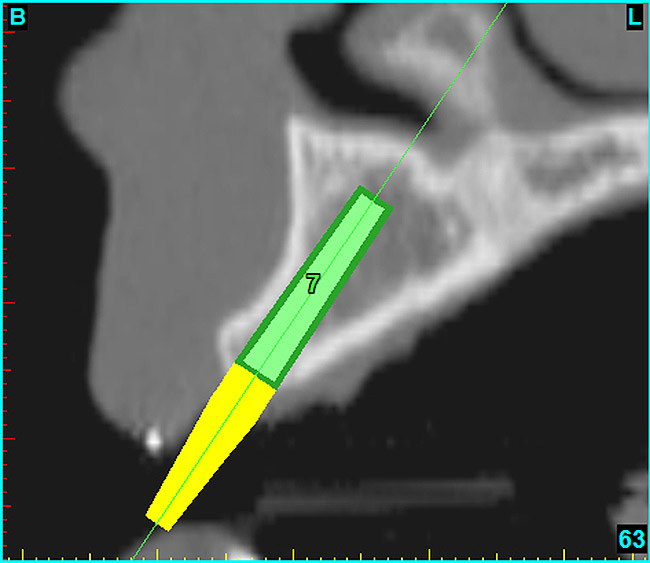

Using the interactive treatment-planning software application, the scan data was assimilated and both potential lateral incisor implant receptor sites were evaluated. It is a.combination of the data and the methodology used to interpret the data that is the basis for defining a new paradigm in diagnosis and treatment planning. Proper evaluation of these images and correct use of the interactive treatment-planning software tools is essential in creating a decision tree of treatment options. First, the data from the scan was reformatted into panoramic, axial, and cross-sectional images. The undistorted cross-sectional images revealed the residual alveolar bone in the area of the right lateral incisor. Then, a simulated schematic implant was placed within the bone with an abutment extension to help visualize the connection to the restorative position of the tooth (Figure 4A). The Triangle of Bone® (TOB), a concept developed by the author to analyze bone quality, quantity, and disposition at prospective dental implant sites using CBCT scans, aided in determining available bone volume by defining a “zone” for proper implant placement18,19 (Figure 4B).

After reviewing the CT data and the decision tree, the bone within the “zone” of the TOB was evaluated and found to be satisfactory for implant placement. Because the goal of implant dentistry is not the implant but the tooth that is placed, true restorative-driven implant dentistry must begin with the assumption that the implant position should remain consistent with the tooth it is replacing, and the final implant-supported restoration.12,22-26 The TOB aids the clinician in understanding the link between the implant position and the desired restorative goal. The base of the geometric shaped “zone” is visualized by starting at the widest area of alveolar bone facially and superiorly. The apex of the triangle is positioned to bisect the alveolar crest (Figure 4B). The TOB, the overlay in the cross-sectional image, reveals whether adequate bone is available for implant placement. It also helps to identify concave facial bone defects, and accurately determine the width of bone at the crest. The author r.commends using an interactive software application that provides the necessary measurement tools to accurately assess the bone anatomy.

After the basic plan had been established, it was re-evaluated using interactive 3D images. The reconstructed 3D view of the maxilla clearly illustrated the extent of the bilateral facial concavities, and the root eminences of the adjacent and posterior teeth (Figure 7A). The placement of the virtual implants then was evaluated to ensure that the facial cortical plate was not perforated (Figure 7B). The implants were labeled individually as “7” and “10,” with the simulated yellow abutment projection indicating the facial-lingual inclination through the bone to the level above the incisal edge of adjacent teeth. The ability to gain a better understanding of these individual root forms can not be underestimated. The dental literature has suggested certain parameters for placing implants near teeth and implants next to other implants. However, there is little scientific 3D documentation to support these suggested rules.5-10 The use of an interactive treatment-planning software application permits closer scrutiny of previously difficult-to-visualize areas, and can now be used to redefine perceptions of spatial positioning of implants, especially when in close proximity to natural tooth roots, vital anatomy, and adjacent implants.27-29

Figure 7a  The 3D reconstruction showed (A) the facial concavities and root eminences, and allowed (B) for evaluation of virtual implant placement to ensure the facial cortical plate was not perforated.

Figure 7a

Figure 7b  The 3D reconstruction showed (A) the facial concavities and root eminences, and allowed (B) for evaluation of virtual implant placement to ensure the facial cortical plate was not perforated.

Figure 7b